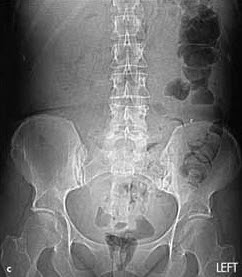

A CT scan of the abdomen and pelvis with oral and intravenous contrast revealed a 5-cm abscess (a) on the left side of the abdomen (A). Adjacent images showed tubular extensions of the abscess, one of which likely represented the appendix. Of note, jejunal bowel loops can be identified by their frond-like appearance on the right side of the abdomen (A, arrow). Normally, the duodenum crosses the midline between the aorta (Ao) and the superior mesenteric artery (S)--a more cephalad image reveals that the most medial extent of the duodenum does not cross the midline (B, arrow). A CT scan performed 6 months earlier during an evaluation for renal stones showed no abscess. Scout view from the prior CT scan demonstrated partially air-filled colon only on the left side of the abdomen (C).

Patients with malrotation or situs inversus present with atypical symptoms because of the abnormal location of internal organs, such as in this patient, in whom the appendix is on the left. Clues can be found in the history--as in this case--as well as in the physical examination. For instance, in patients with situs inversus, percussion of the abdomen reveals that the liver is on the left side. Radiography with exquisite attention to labeling is diagnostic. Bowel malrotation can be suggested on plain film or CT; barium studies are confirmatory.